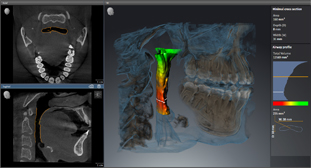

Анализ дыхательных путей с SICAT Air

Специальная функция привлечёт в вашу клинику людей с проблемами дыхательной системы.